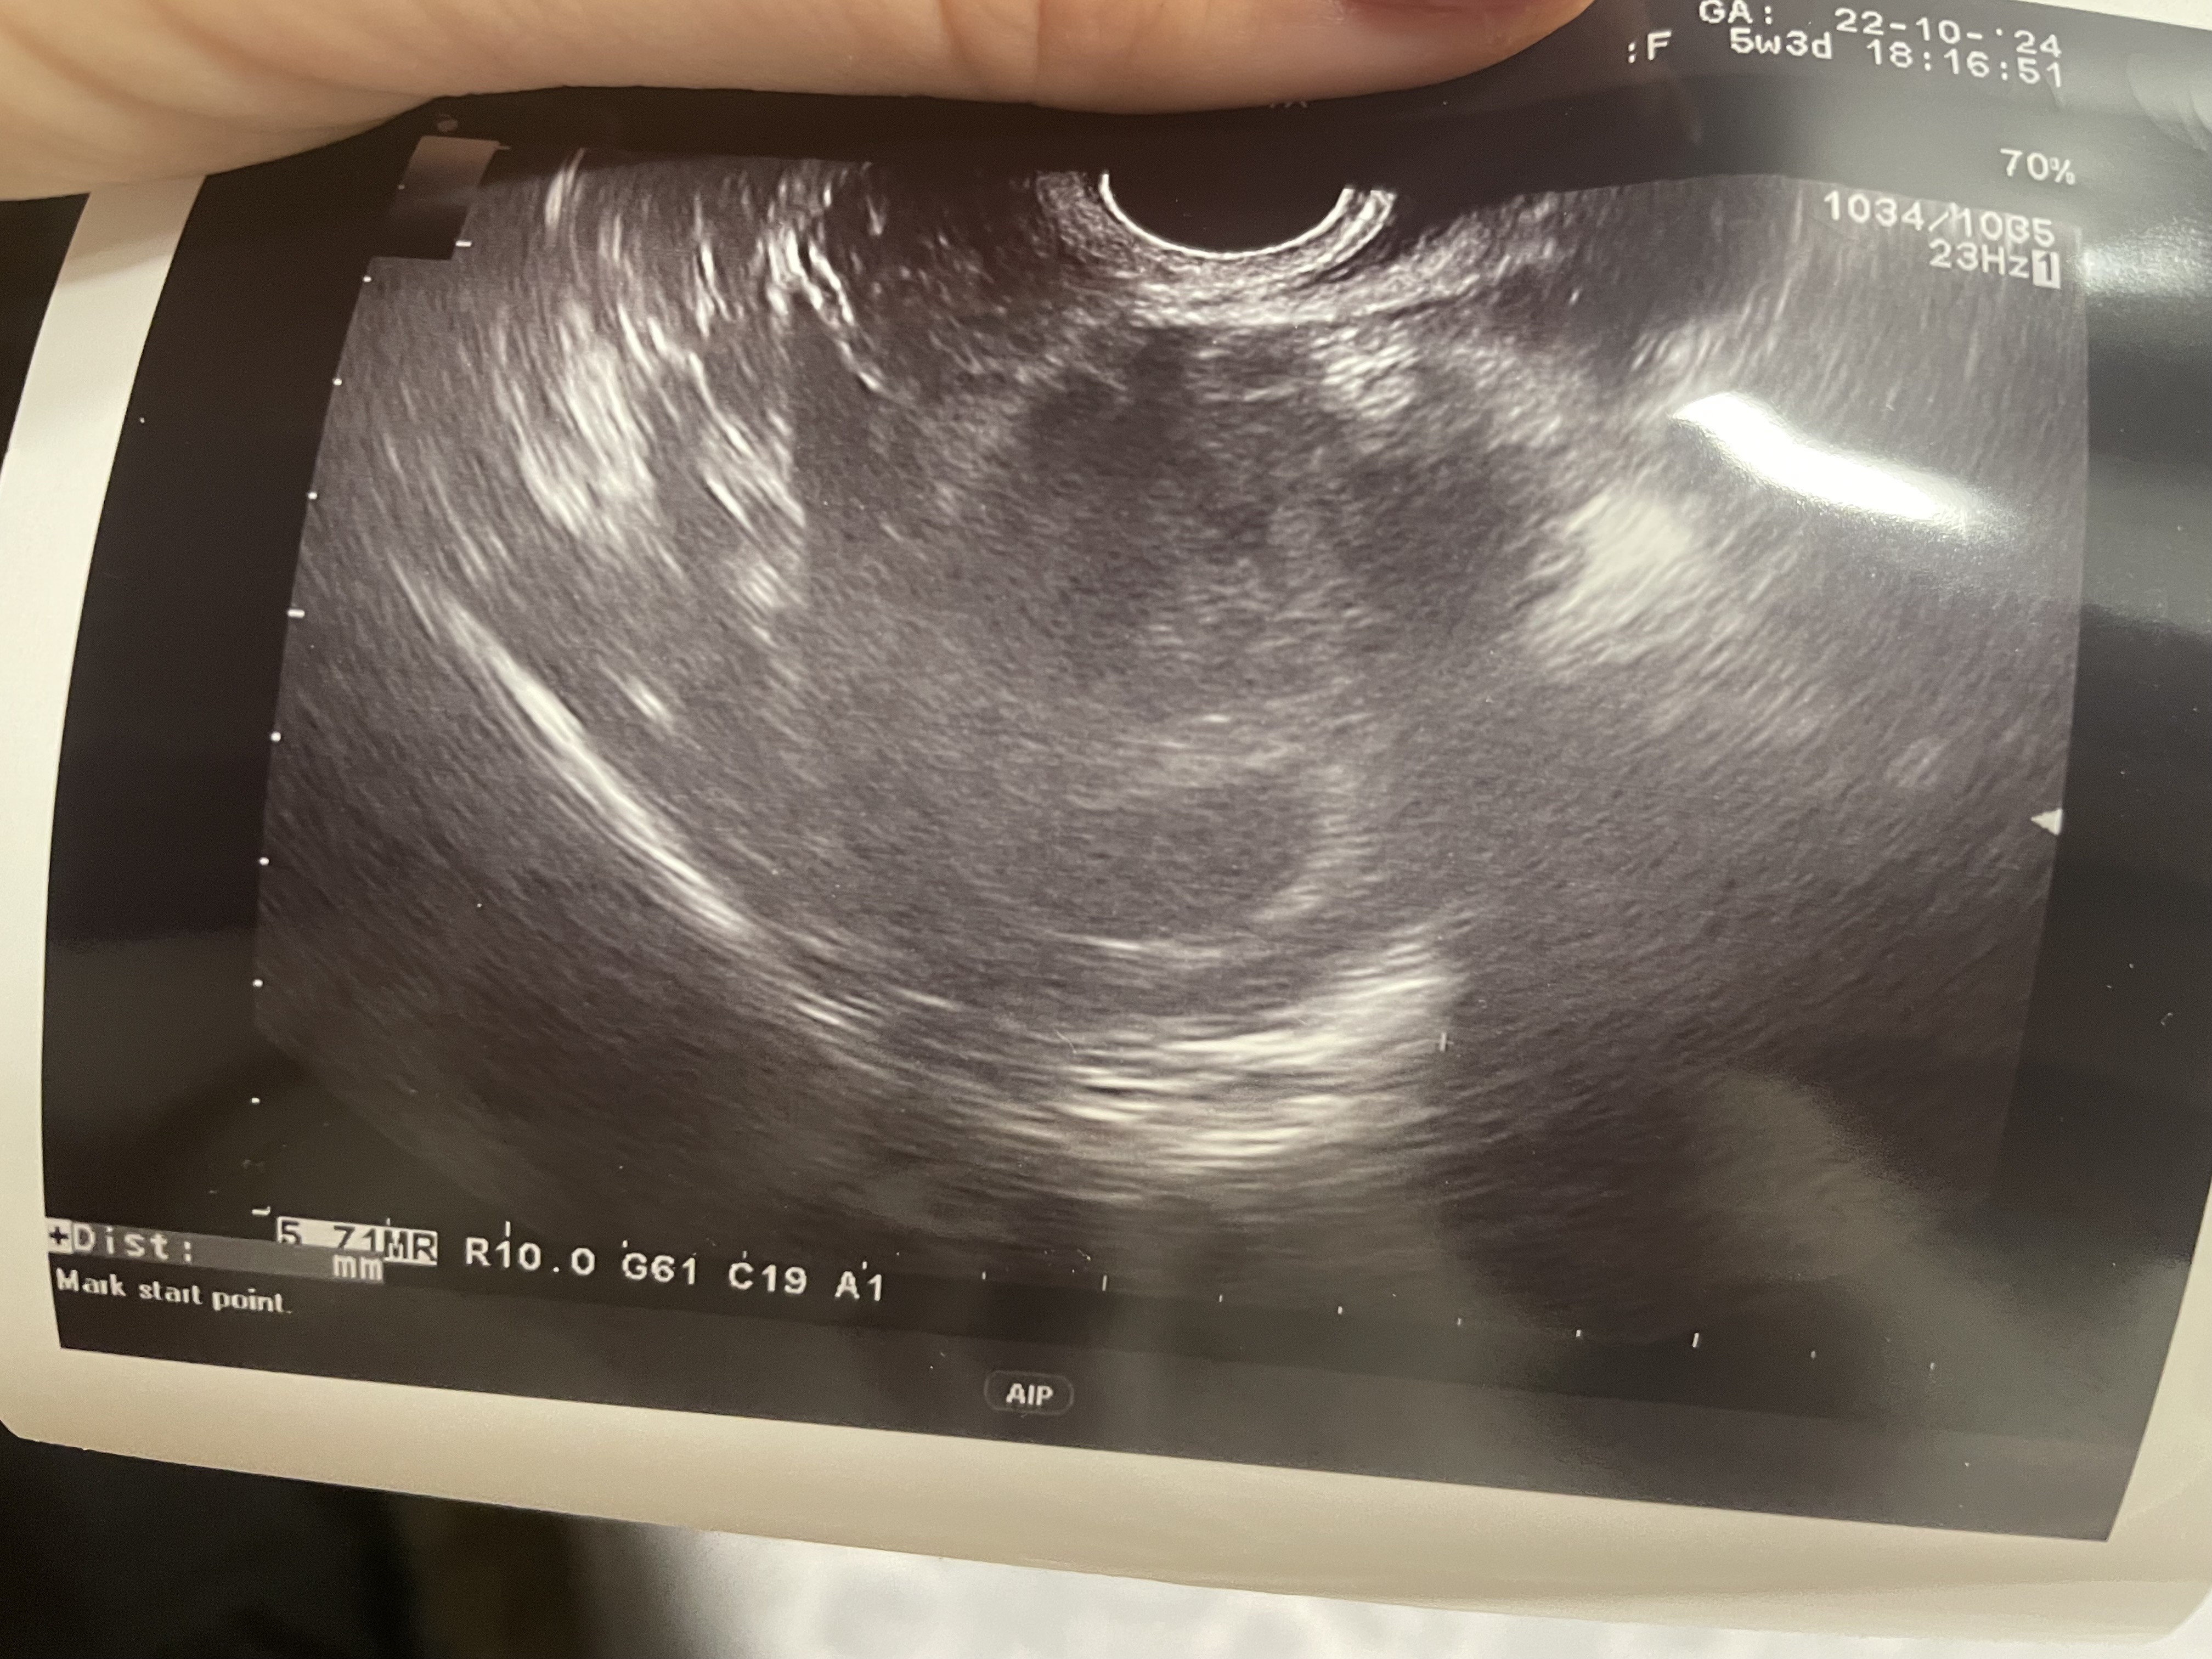

USG 5 tc brak zarodka, wysoka beta

Lekarz kazał mi przyjść na usg 22 października czyli 5+3 tc. Na USG pęcherzyk brak zarodka. Kazał powtórzyć betę. Zrobiłam 23 października wynik 40057,0 i drugi 25 październik wynik 48780,0. Przy takich wartościach powinno już być na usg? Martwię się. Idę na usg w pon 28 października.

Puste jajo płodowe?

Ale niewyraźne to USG. Masz wymiary pęcherzyka ciążowego? W pęcherzyku ciążowym był pęcherzyk żółtkowy?

Bhcg masz już wysoką, przy poziomie 10000 powinnien już być zarodek. Nie wygląda to dobrze :( ale to zdjęcie z USG jest bardzo niewyraźne, co może wskazywać na to, że twój lekarz ma słaby sprzęt, złą ostrość i dlatego nic nie widział.

Nawet nie wiem co jest ma tym zdjęciu. Bo równie dobrze mógł to być jajnik. Lekarz nie mierzył pęcherzyka? Powyżej 25 mm można uznać, że jest puste jajo. Beta już bardzo wysoka więc zarodek powinien być.

Nie pamiętam ile miał pęcherzyk ale gin mówił że w normie. Stwierdził że jestem za wcześnie. Tylko zastanawiam mnie tak duża beta